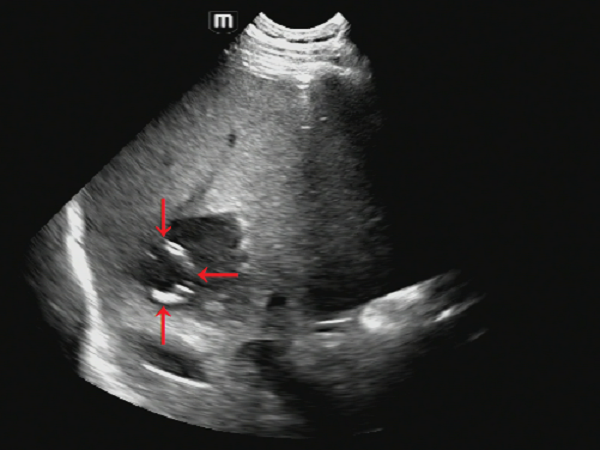

操作过程:患者左侧卧位,对右肝前叶上段脓肿选择穿刺点,常规碘伏消毒后铺巾,超声引导下以1%盐酸利多卡因逐层浸润麻醉至肝包膜,选8F套管针直接穿刺法(一步法)穿刺,超声监视下引流管避开肝内血管及胆管,到达脓腔后拔出穿刺针及支撑管(图2、图3),用注射器抽出脓液10ml后(图4),接引流袋固定。

图3 红色箭头所指白色线圈为拔出穿刺针后留置的引流管